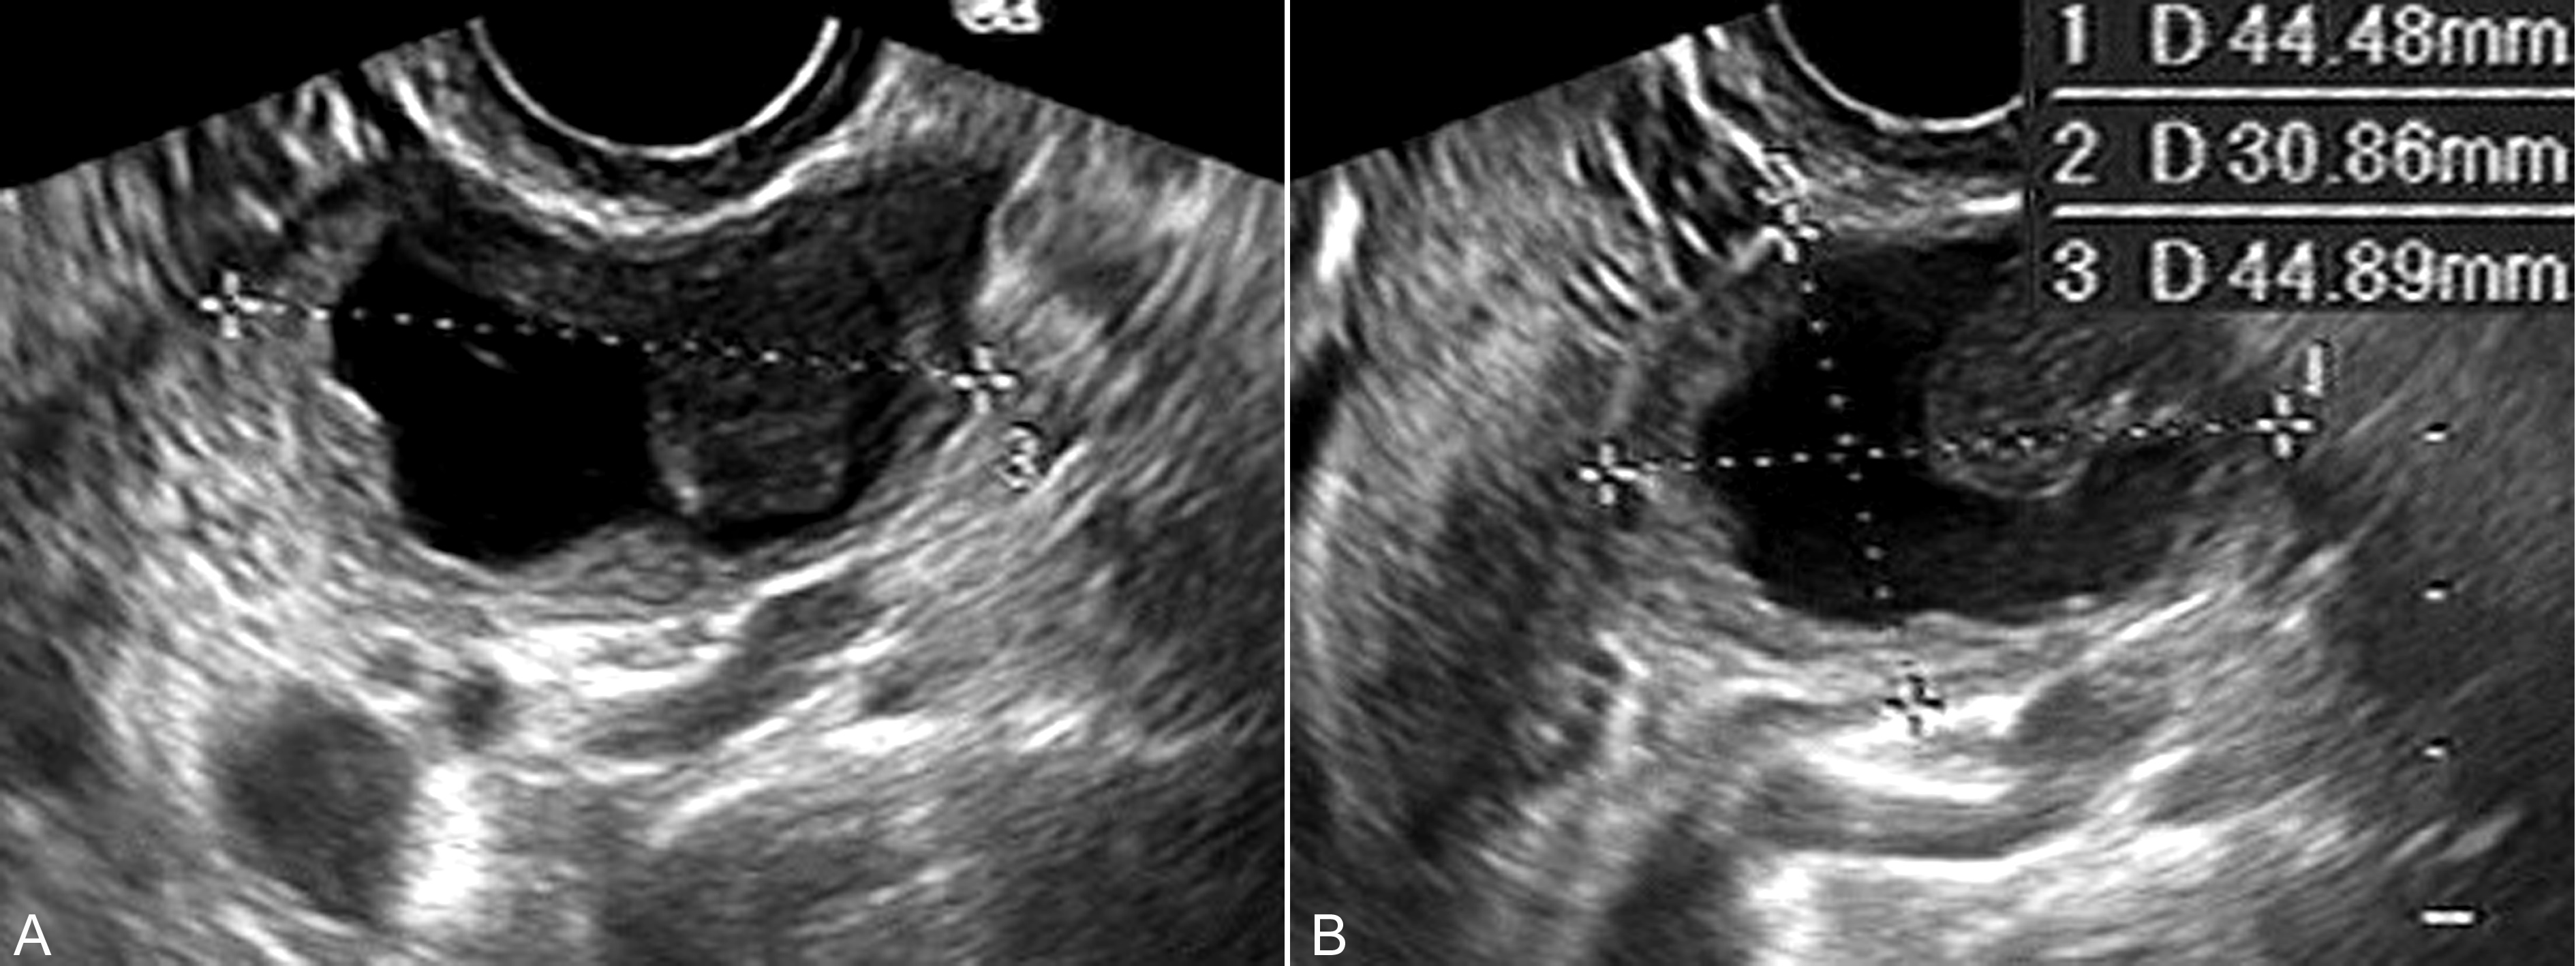

超声显像检查声像图特点与妊娠子宫大小有一定关系,子宫较大时瘤体常由于受压、推移而与非孕期检查显示不同。但恶性肿瘤的一般声像图特点仍可显示,如形态不规则,边缘不清楚;囊性的瘤体显示囊壁厚薄不一(图1A、B),并可显示不规则的乳头状突起而形成液体-实性混合型回声(图2C、D),囊内无回声区内常可显示不均匀的点状回声,囊壁或乳头状突起的回声内常可显示血流;实质性恶性肿瘤的声像图特点更为明显,形态不规则,边缘不清楚,内部回声强度及分布不均匀,并可以显示不规则、模糊的低回声区,CDFI检查内部多有不均匀分布的血流显示。有时腹腔内可合并少量积液。

图1卵巢恶性粘液瘤声像图:宫旁瘤体显示瘤体回声,形态不规则,边缘不清楚;囊壁厚薄不一